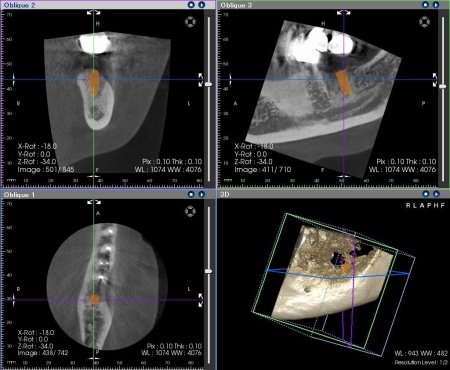

その後、歯科用CT撮影を行い、顎の骨の量や形、神経や血管の位置を立体的に確認しました。撮影したデータをもとに、インプラントを埋め込む位置や角度、深さについて事前に設計を行い、安全性と噛み合わせのバランスを考慮した治療計画を立てます。

インプラントの埋入設計をしました。